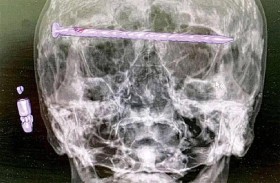

«مسمار» داخل جمجمة رجل

اكتشف أطباء روس مفاجأة صادمة عند فحص رجل، يبلغ من العمر 78 عاما، إذ تبين وجود مسمار طوله 15 سم مستقرا في رأسه.ووفق موقع "روسيا اليوم"، أجريت عملية جراحية للرجل، الذي ينحدر ... إقرأ المزيد